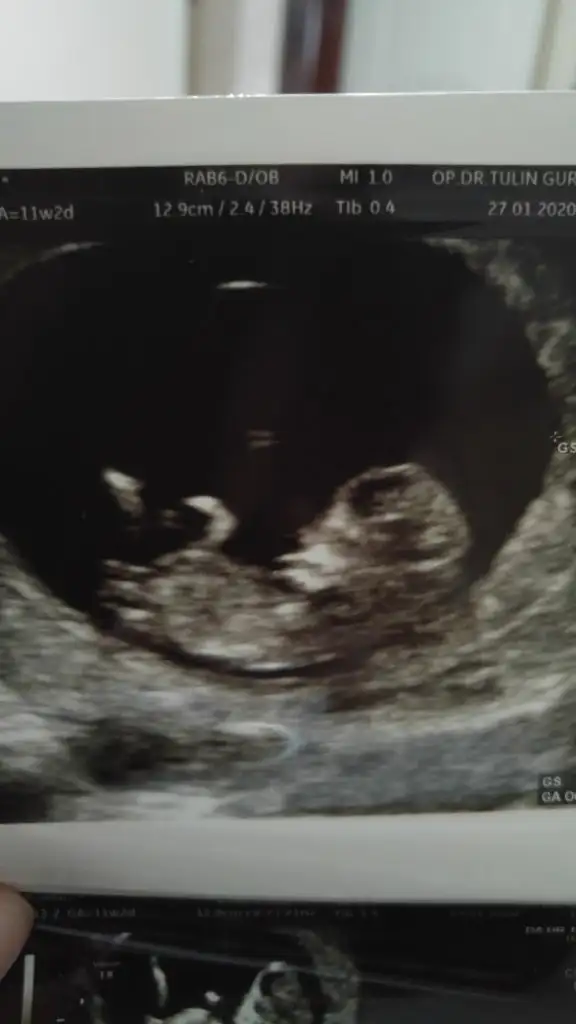

dr soylemeden siz gorun genital nub teorisi ( bebegin cinsiyeti)

Biraz daha belli olmuştur tekrar bakma şansınız olursa çok sevinirim 12.haftada dr hala erken dedi cinsiyet için

• 20200127_143851_001.webp

20200127_143851_001.webp

19,4 KB · Görüntüleme: 48